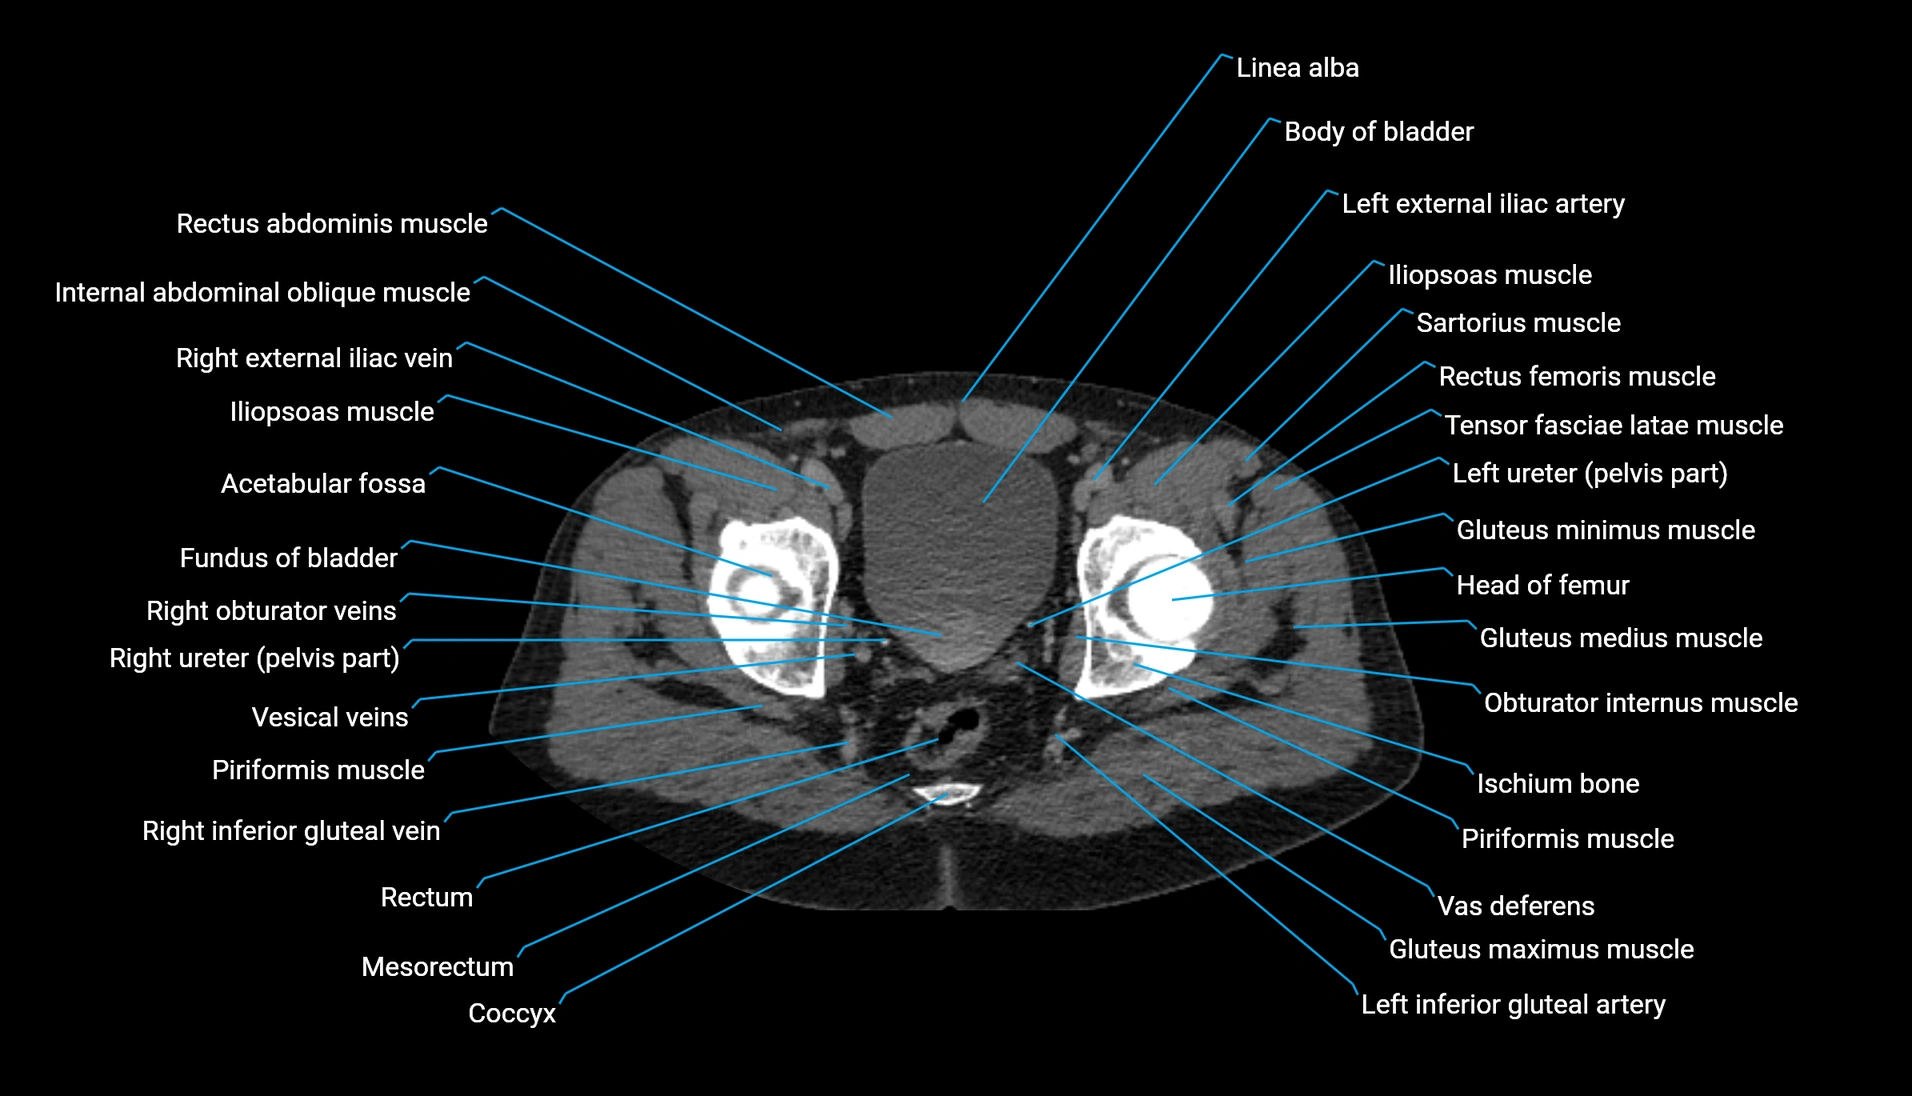

CT Appearance

Non-contrast CT:

-

Demonstrates cortical bone of acetabular rim in excellent detail

Detects fractures, dysplasia, retroversion, or bony overcoverage (pincer impingement)

3D reconstructions used in preoperative hip surgery planning

CT VRT 3D image

CT image